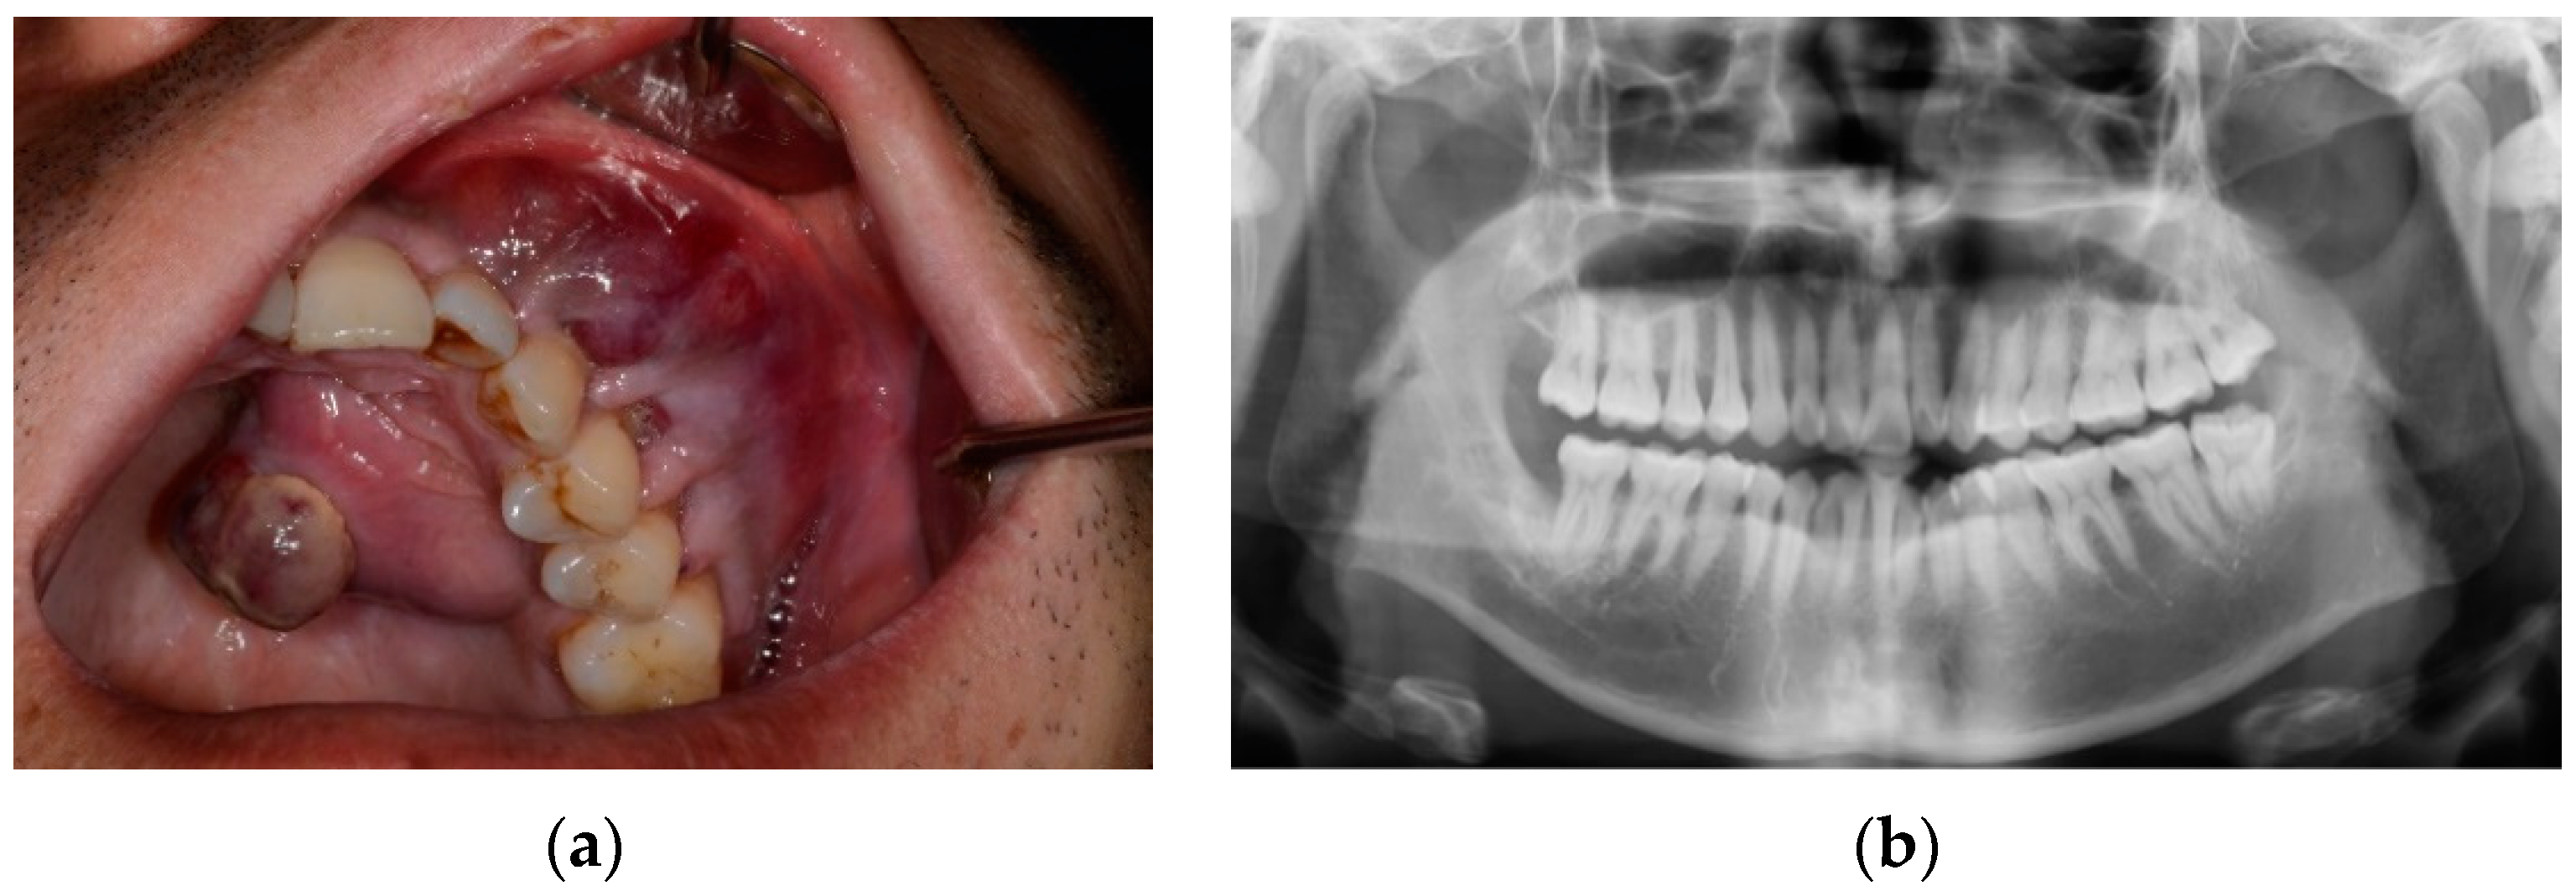

2. Case Presentation